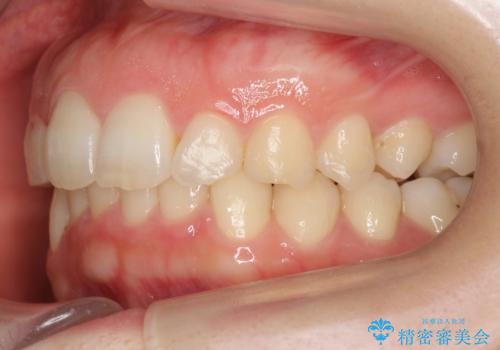

- 前歯のがたがたと出っ歯を主訴に来院。

CTを撮影したところ、臼歯部の頬側の骨の厚みが非常に大きく、通常では考えられない量の歯列の拡大が可能でした。

今回は健康を損なわずに非抜歯で治療が可能でしたが、

歯ぐきや骨の厚みが薄い他の患者さんでは難しいです。

左上5は180度捻転していましたので、そのまま並べています。

遠心移動などは行わず、IPRと拡大のみで治療を行いました。

一般的に非抜歯矯正を無理に行うと、口元がモッコリ出てしまうことがあります。しかし、今回は前歯を前に出さないような設定にしており、口元が出ることもありませんでした。